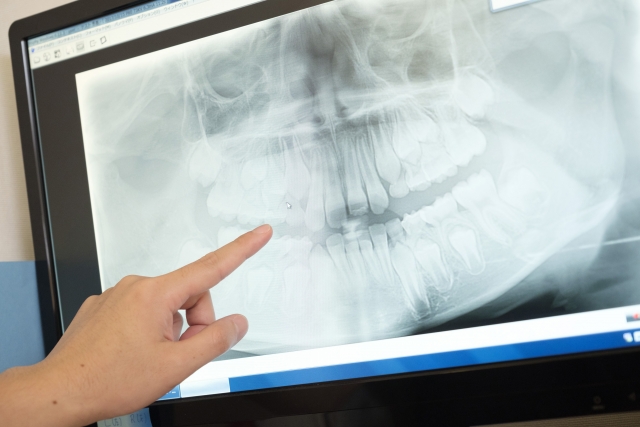

インプラント治療についての基礎知...